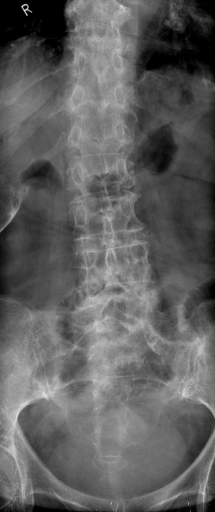

In this section, we report two series of experiments. The first one verifies the correctness or reliability of the micro-DE algorithm to find optimal projections compared to an exhaustive search when we are looking for 4 optimal projection angles out of 16 equidistant angles. In the second experiments, we still provide the results for exhaustive 4/16 selection but examine the evolutionary approach to get 4/180 and 8/180 to investigate the reconstruction accuracy of the micro-DE via correlation of the input image and the reconstructed image using 4/16 (exhaustive), 4/180 (micro-DE) and 8/180 (micro-DE). To conduct the experiments we used 50 images from IRMA dataset [34, 35], a benchmarking collection of 14,400 x-rays images. We selected 10 random classes out of 58 classes, and for each class, we randomly drew 5 images to be used in our experiments. Figure 4 shows the images we have used.

![]() |

[0∘, 79∘, 101∘, 157∘] with |

| [0∘, 68∘, 112∘, 169∘] with | |